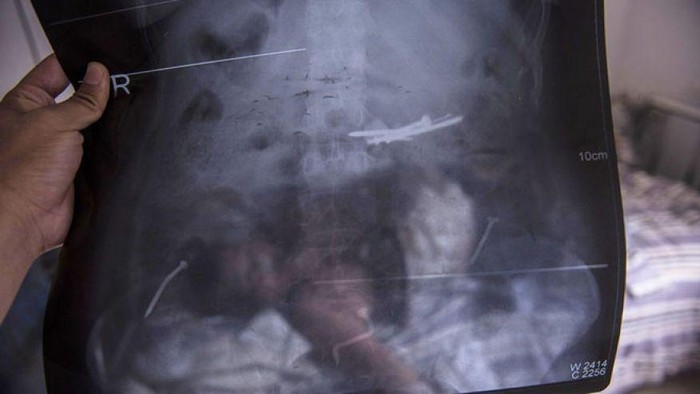

Dalam kurun dua tahun belakangan Li ternyata mengidap sebuah gangguan mental langka. Gangguan mental itu mendorong Li untuk terus memakan beling dan juga logam. Bahkan dua tahun ini ia diperkirakan telah menelan setengah kilogram paku.

Mengetahui hal itu, dokter lantas segera melakukan tindakan operasi untuk meredakan keluhan si pasien. Benar saja, setelah 3,5 jam, tim dokter mengaku berhasil mengeluarkan 8 paku dari dalam tubuh Li. Demikian seperti dikutip dari Foxnews, Kamis (13/8/2015).